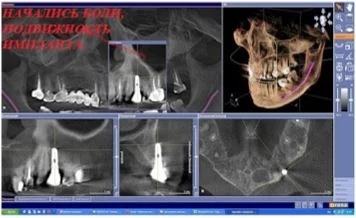

Компьютерная томография - это ключевой метод обследования в имплантологии

Воссоздавая орган (зуб) или даже совокупность органов, необходимо предельно точно знать исходную ситуацию. Корни зубов, каналы зубов, крупные сосудисто-нервные пучки, идущие внутри костной ткани, верхнечелюстная пазуха во всех подробностях и т.д. - в неискаженном виде все это можно увидеть только на компьютерной томограмме. Стоит ли говорить, что все эти структуры важны для имплантации, так как могут быть легко поврежденфы в ходе операции.

Как получить гарантированный результат имплантации? При помощи компьютерной томографии!